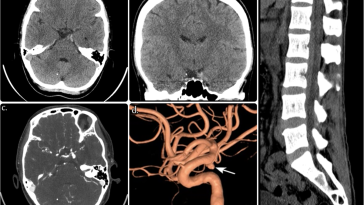

Fatal Ruptured Posterior Communicating Artery Aneurysm A Stark Reminder of Medical Vulnerability